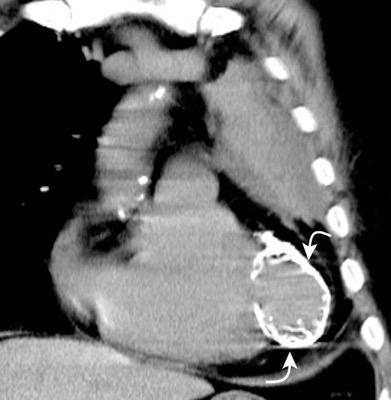

Raro. (2-9% de los T. tímicos). Asintomático. Contiene grasa (hasta 90%) y tejido timico (10-33%). Pueden ser muy grandes y confundirse con cardiomegalia. La tomografía “clásica” muestra los límites de la silueta cardiaca. (flechas)